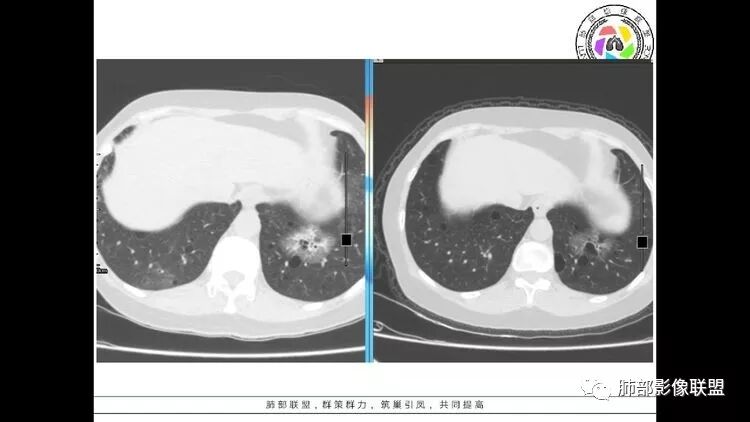

患者中年女性,因右眼红痛1天就诊。胸CT:双肺多发囊性变及结节影,囊以中下肺为多,部分囊内可见分隔及肺动脉,结节部分为实性,部分为混合性,边缘光滑,未见明显毛刺、棘突、胸膜牵拉及血管集束征象。双中下可见支气管扩张及树丫征。淋巴结无明显肿大。综合考虑:一元淋巴细胞间质性肺炎。多元鉴别肺腺癌并转移等恶性病变。

中年女性,因“角膜炎”入院,自用眼液2年,(眼干?)肺部:双肺多发类圆形薄壁气囊+实性结节+GGO,下肺分布为主,纵隔淋巴结肿大,考虑淋巴系统增殖,LIP可能性大,可能继发于干燥综合症;左肺下叶的混合磨玻璃结节形迹可疑,边界清晰,内部疑似空泡,扩张扭曲支气管,极像肺癌,伴双肺转移?待排吧